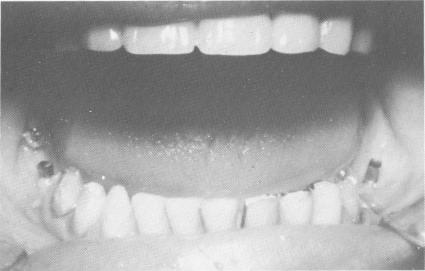

Restoring a Class III malocclusion to a Class I relationship with maxillary and mandibular blades

In Linkow's opinion, the transition from a Class III to a Class I relationship should be accomplished by using the prostheses to restrict the closure of the mandible and by leaving a freeway space between